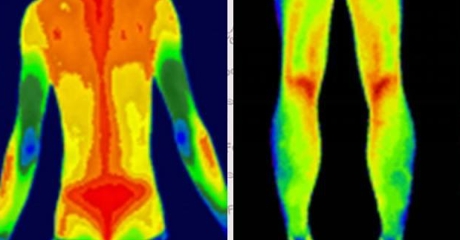

圖為紅外熱成像檢查

紅外線熱成像檢查方法:使用醫(yī)用紅外熱像儀對(duì)病人進(jìn)行檢查。檢查室室溫維持在22~24℃,空氣無(wú)對(duì)流、無(wú)陽(yáng)光直接照射。受檢者前1天晚上禁止吸煙、飲酒等,檢查前充分暴露后定位掃描區(qū)域,于安靜狀態(tài)下休息15min后進(jìn)行檢查,檢測(cè)定位區(qū)域局部體表平均溫度。所有納入病人均在入院以及末次治療后1周、1月、6月進(jìn)行紅外熱成像檢查。

紅外熱像技術(shù)圖像分析和評(píng)價(jià):將使用紅外熱成像儀攝像機(jī)獲得的所有入組病人的腰背部圖像數(shù)據(jù)用配套分析軟件轉(zhuǎn)換為灰度數(shù)字圖像,獲得紅外熱像技術(shù)平均溫度并進(jìn)行統(tǒng)計(jì)分析。